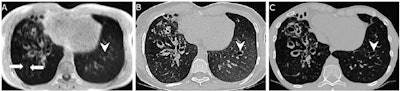

Longuefosse and colleagues investigated whether synthetic CT images created using a generative adversarial network (GAN) algorithm to process short-echo MRI images could serve as a viable alternative for imaging cystic fibrosis. The team trained the GAN on paired MRI and CT sections and tested it along with an external set of data.

Next, the investigators conducted a study that included 110 patients with cystic fibrosis who underwent both short-echo MRI and CT on the same day between January 2018 and December 2022. The training set consisted of 82 patients and was seeded with 33,002 paired MRI and CT exams; the test set included 28 patients; and the external data set included 46 patients.

The researchers assessed image quality by measuring contrast-to-noise and signal-to-noise ratios and overall noise, as well as features such as artifacts. They found that synthetic CT's performance bested both real CT and MRI when it came to contrast-to-noise ratio and overall noise.